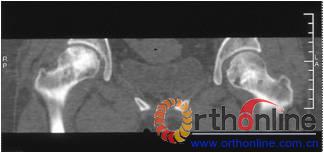

病灶修复情况比较,加用BMP2组病灶修复的完全性及硬化骨数量普遍优于未加BMP2组。(图3)

图3-2 女,30岁,SARS患者骨坏死,(1)术前MRI示双侧骨坏死;右Ⅱc期C3型,左Ⅱb期B型,打压植骨术(加BMP2),(2)5年后CT显示病灶修复好,关节功能优